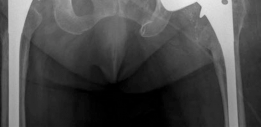

--- Fig. 20.11 Cross-table lateral left hip radiograph—ace-tabular component has flipped into retroversion with marked posterior bone loss #### Preoperative Planning